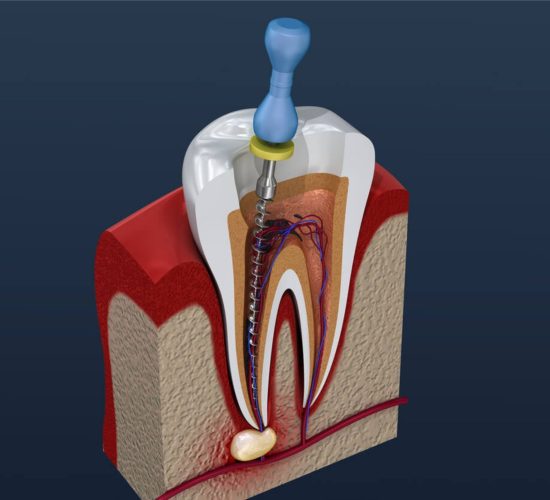

Endodonti (Kanal Tedavisi)

Endodonti, diş minesi, dentin ve diş pulpasının muayenesi ve tedavisine odaklanan diş hekimliği uzmanlık alanıdır.